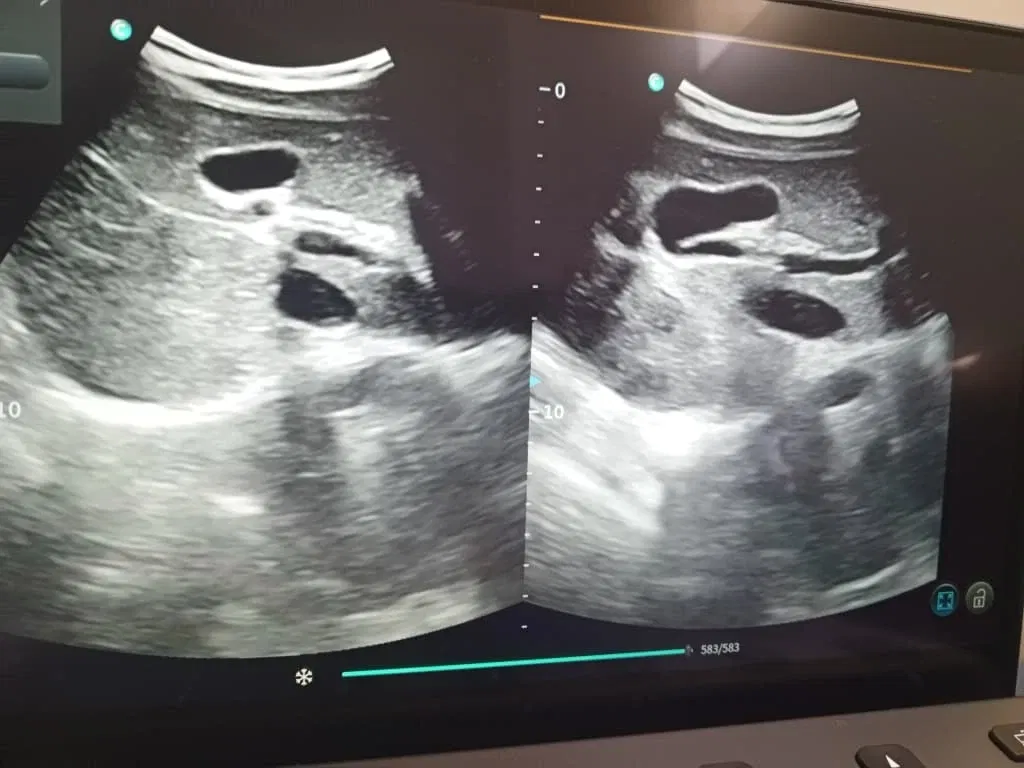

Estuve desde las diez y la consulta comenzaba a la 1. Mi hija llegó minutos antes. Yo aproveché y pase a consulta y pasé por un dolor en el talón que no se me quita. Me dieron orden para rx de pie y alcance número también.

Yesterday was a bit exhausting. I had to go to the CDI to sign my daughter up for an abdominal echocardiogram. They told me I could go early to sign up and then come back later.

I was there from ten o'clock, and the appointment started at 1. My daughter arrived a few minutes early. I took advantage of the situation and went to the consultation and mentioned a pain in my heel that won't go away. They gave me an order for an X-ray of my foot and a number as well.